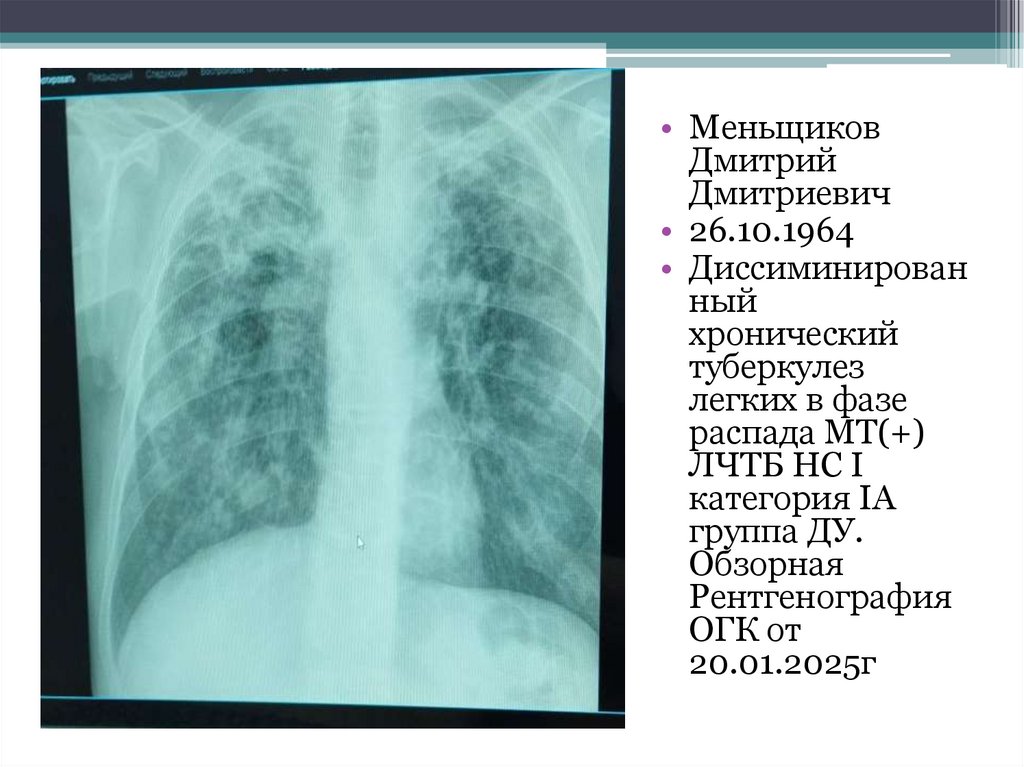

• Меньщиков

Дмитрий

Дмитриевич

• 26.10.1964

• Диссиминирован

ный

хронический

туберкулез

легких в фазе

распада МТ(+)

ЛЧТБ НС I

категория IА

группа ДУ.

Обзорная

Рентгенография

ОГК от

20.01.2025г